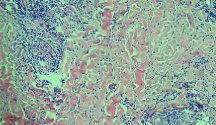

Leishmaniasis background and histology presentation. The World Health Organization (WHO) has selected cutaneous leishmaniasis as a neglected tropical disease (NTD) with growing, uncontrolled, and ignored infection affecting millions of people every year [14, 9]. It is unfortunately one of the world’s most neglected poverty-related diseases, affecting the poorest people in developing countries and it is associated with risk factors like malnutrition, immune system deficiency, migration, inadequate education, illiteracy, gender inequality, and a shortage of services [1]. Furthermore, only eight countries in the world contribute to 90% of leishmaniasis cases: Afghanistan, Algeria, Brazil, Iran, Pakistan, Peru, Saudi Arabia, and Syria [12]. It is a vector-borne infection caused by the protozoan parasite Leishmania. The vector is the female sand-fly. The lesions of cutaneous leishmaniasis vary in presentation ranging from a single self-limited skin lesion to multiple large destructive and ulcerated lesions on mostly the exposed parts of the body such as face, forearms, and lower legs [2]. Skin biopsy is considered the gold standard method for confirmation of diagnosis. The presence of large epitheloid granulomas and small hematoxylinophilic LD bodies (that are round, uniform in appearance, intracytoplasmic and sometimes distributed around the outer rim of the vacuoles) is critical for diagnosis and confirmation of leishmaniasis [4]. Large granulomas are visible at 10X but the smaller hematoxylinophilic bodies (around 3-4mm in size) are usually visible at 40X and can easily be missed if they are few in number, leading to misdiagnosis. Specialized dermatopathologists are the only ones who can diagnose these accurately based on patient history, clinical features, and laboratory diagnosis. It is thus critical to share the digitized slides of these cases from rural poor remote areas with dermatopathologists (mostly residing in urban centers) for quick diagnosis and accurate management of the patient.

We demonstrate our WSI creation workflow on Leishmaniasis cases, as shown in Figures 1 and 4. An expert pathologist reviewed the cases and annotated granulomas as well as LD bodies on the stitched images and our generated images in Figure 4. To show generalizability of our approach, we also show results on core biopsies of breast, duodenum, stomach, liver, and lymph nodes (Figure 5).